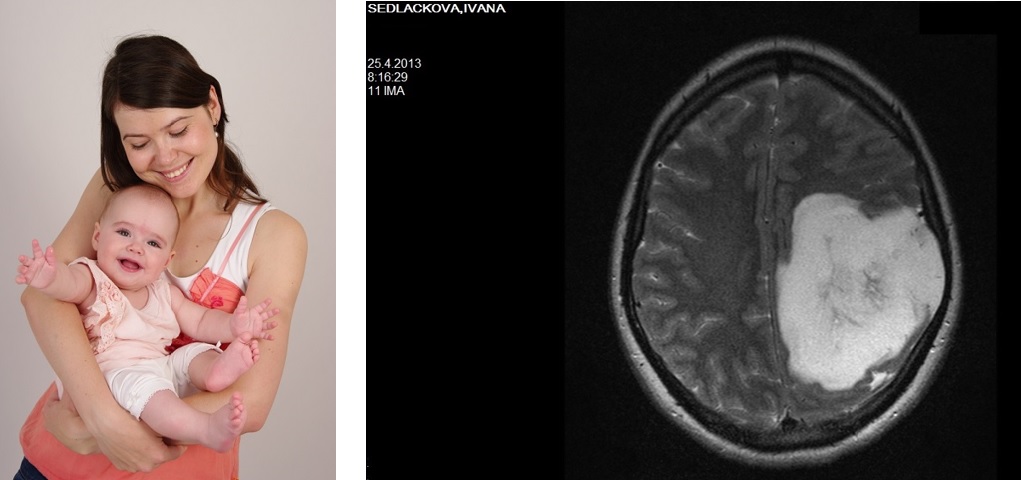

Knížka začíná dnem, kdy jsem jela na magnetickou rezonanci. Co vám tedy začne vířit hlavou, když se dozvíte, že v ní máte obrovský nádor?

Má první myšlenka poté, co jsem spatřila snímky z magnetické rezonance patřila Magdě. Mé dcerce, která na mě doma čekala, až se vrátím a nakojím ji. Doktoři ale měli jiný názor. Bylo mi 28 let.

Deník o sobě, o svém nádoru a o svém okolí, které se s mou diagnózou muselo také vypořádat, jsem začala psát pár týdnů po operaci mozku v roce 2013. kdy jsem vlivem léků, hormonů, zastavovaného kojení, nevyspání se a stresu měla změněné vnímání. Tehdy jsem měla zbystřené smysly, proto je deník i o tom, jak prodělat rakovinu mozku a (ne)zbláznit se. Díky tomu, že jsem si z počátku nepřipouštěla závažnost nemoci a soustředila se na rychlé uzdravení a návrat domů za dcerkou, je knížka i přes své téma místy veselá.